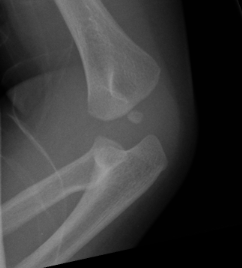

1 year old male: C 5 year old female: CR